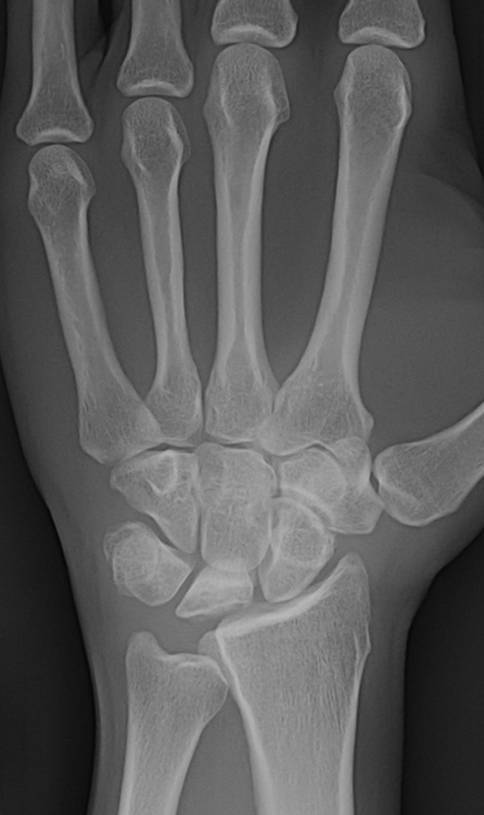

Welche Diagnose stellen Sie in diesem Fall von attraumatischen Handgelenkschmerzen?